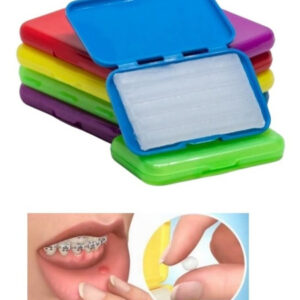

ALASTIC MEDIO PERLADO X 1.5MTS- MORELLI

La cadena de elastómeros ortodónticos, son empleados como promotores de fijación de arcos ortodónticos a las ranuras de los brackets, promoviendo el trazado de los elementos dentales y transferencia de las fuerzas aplicadas por los arcos para corrección de las maloclusiones.